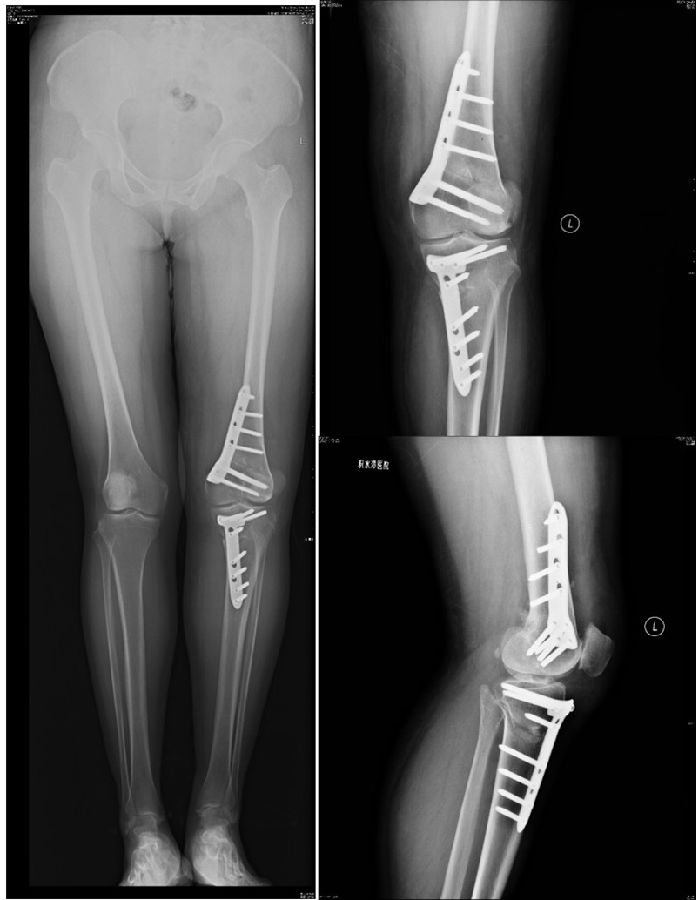

以两例病例展示术前设计的五步。患者一,女性,42岁,左膝疼痛2年,加重1年。

量股骨远端外侧角和胫骨近端内侧角,判断畸形在股骨、胫骨还是关节内。此患者股骨侧有畸形,LDFA=76°,MPTA=81°,无关节内畸形。

以股骨侧合页为旋转中心,以股骨头中心到合页的距离为半径,进行旋转,直到该线段与目标力线相重合,此时重合角度即为股骨需要闭合的角度,同时胫骨侧也能计算出开放的角度。此患者需要股骨闭合14°,胫骨开放8°。

术后影像